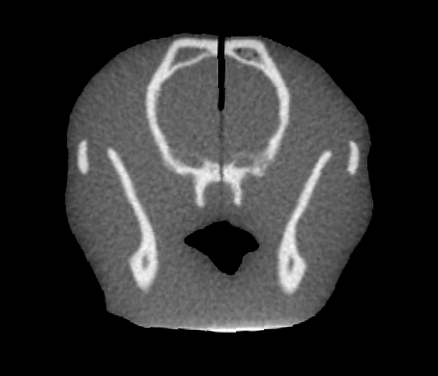

This study used the Kilovoltage Optimized AcceLerator Adaptive therapy (KOALA) x-ray system at the University of Victoria [13], which is being developed with the aim to treat canine cancer patients with kilovoltage (kV) x-ray beams. The phantom needed to mimic a dog structurally and in radiographic properties, as well as incorporate some method of measuring dose delivery. It is necessary to validate KOALA’s ability to effectively treat deep-seated tumours, so a glioma patient was used as a model for UPDOG. Computed tomography (CT) scans of the patient were obtained from a veterinary clinic and segmented using Python and 3DSlicer (version 5.6.2, Brigham and Women’s Hospital, Boston, MA) [14]. The bite block, thermoplastic mask, and breathing tube used to acquire the CT scans were manually removed, and the image was separated into two segments of bone and soft tissue (Figure 1). The segments were converted into stereolithographic (STL) files in 3DSlicer and smoothed using Fusion360 (version 16.9.0.2204, Autodesk, Mill Valley, CA). A 3×6×0.07360.073\times 6\times 0.073 × 6 × 0.07 cm slit was added into the middle of UPDOG’s head at the location of the glioma tumor to accommodate an RCF.

Refer to caption

Figure 1: A slice of the CT scan of the canine patient, with the bone (green) and soft tissue (gray) segments, contoured in 3DSlicer. The bite block, which has a similar density to bone, is shown in white. The immobilization thermoplastic mask seen around the dog patient was not included in phantom design.